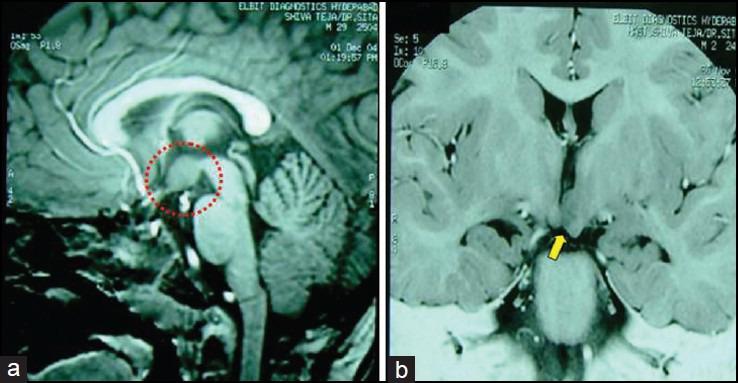

Hypothalamic hamartomas (HH) are ectopic masses of neuronal and glial tissue most commonly presenting with medically refractory gelastic seizures with evolution to other seizure types. They are also associated with cognitive and behavioral problems to varying extent. Surgery has been found to improve quality of life in more than 50% of patients.

Medically refractory epilepsy associated with behavioral and cognitive dysfunction is the most common presentation of HH. Open surgical resection is safe with favorable outcome of epilepsy in 50% with significant improvement in behavior and marginal change in cognitive functions.